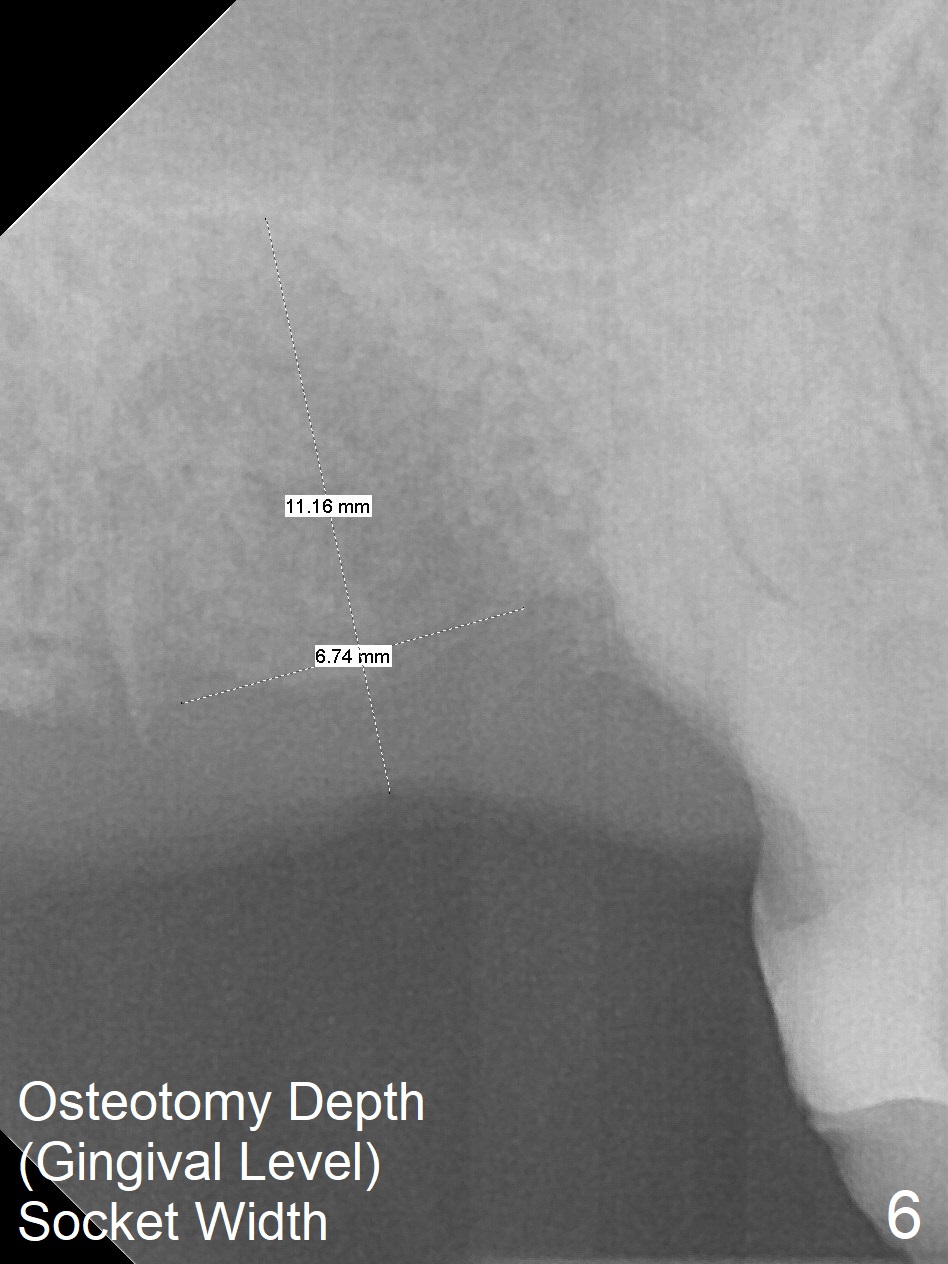

A 65-year-old man returned to finish LR and LL quadrant SRP a few weeks post SRP for UR quadrant and #2 extraction (Fig.1-2). He returns for UL SRP tomorrow ~ 3 months post extraction (Fig.4). Although the patient cannot remember whether socket preservation is done or not, there appears to be bone graft in the socket. The ridge is wide. It seems reasonable to expand and condense the socket using Magic Split and Expanders (flapless). If the patient cannot tolerate tapping, use DIO Bone Expanders. A 6.5x9 (3) mm Magicore will be placed (Fig.5,6).